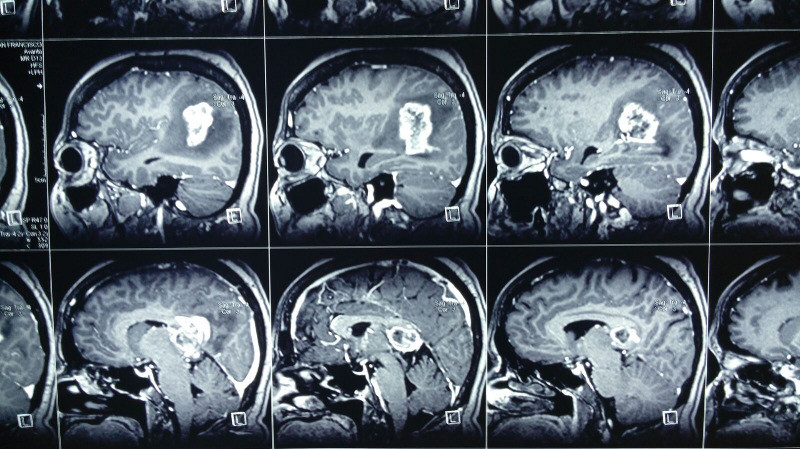

Paciente femenina de 55 años con tumoracion pineal con extencion superior lateral derecha